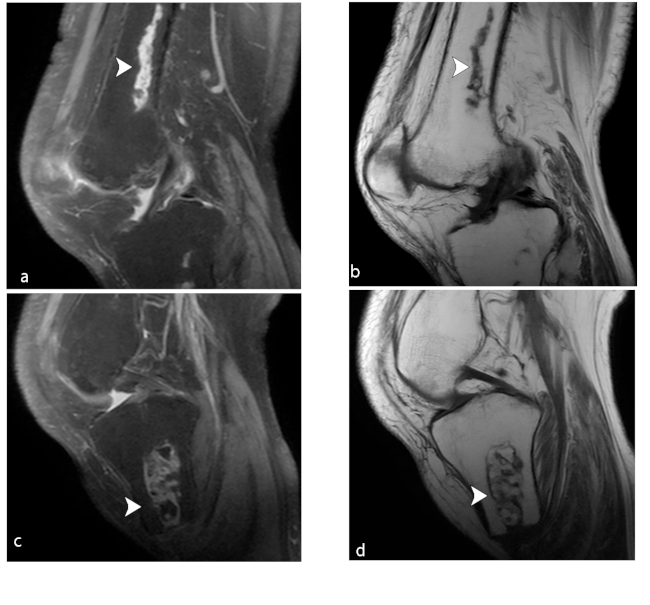

Como ya se ha mencionado, los infartos óseos se definen como la isquemia ósea de la metáfisis y diáfisis de un hueso, con su consiguiente destrucción de la arquitectura ósea, dolor y pérdida de la función.

Fisiopatológicamente hablando, el infarto comienza en el momento en que se interrumpe el suministro sanguíneo en una sección del hueso, lo que da a lugar un núcleo central necrótico rodeado de zona isquémica hiperémica. El déficit del flujo sanguíneo puede ser causado ya sea por compresión vascular, por trauma, por la oclusión de los vasos por burbujas de nitrógeno (enfermedad de Caisson) o por alteraciones de células falciformes. La enfermedad de Gaucher y anemia de células falciforme tienen mayor tendencia al desarrollo de infartos óseos.

En los hallazgos por imagen, los infartos se diferencian del resto de las lesiones de médula ósea por la persistencia de la señal de la médula normal en el centro de la lesión (►Fig. 15) debido a que la médula no se sustituye.30

Las características por RM son bastantes distintivas, evidenciándose una lesión de bordes serpiginosos (patrón geográfico) de baja señal ponderada en T1 (►Fig. 16) debido al tejido de granulación y en menor medida a la esclerosis, pudiendo realzar tras la administración de contraste endovenoso (►Fig. 17). En secuencias ponderadas en T2, el infarto agudo se observa como un área inespecífica de alta señal, a veces con signo de doble anillo en relación a anillo interno hiperintenso por el tejido de granulación, visualizado en secuencias de DP con supresión grasa. Los sitios más frecuentes son metáfisis distal femoral, tibia, y húmero.31

Se debe mencionar que existen diagnósticos diferenciales en referencia a lo radiológico, incluyendo algunos tumores y la osteomielitis, e incluso la posibilidad de malignización en la zona de infarto óseo previo.

Al momento no existe un tratamiento específico, por lo que el enfoque es principalmente paliativo para aliviar el dolor óseo, realizando seguimiento radiológico ante la posibilidad de un diagnóstico diferencial neoplásico.31